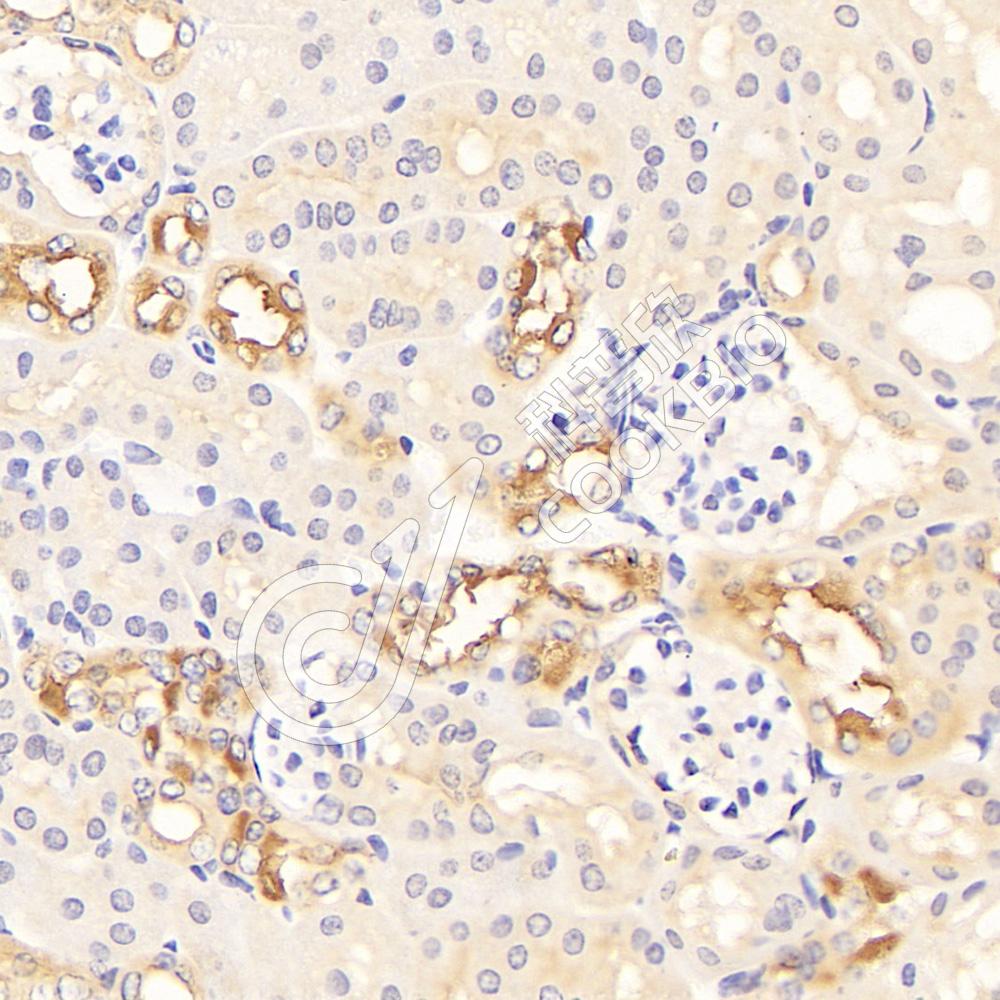

IHC检测TMEM213蛋白(货号 K1340077).

样品: 小鼠肾, 4%多聚甲醛 (货号KSG1101) 固定12-24小时.

抗原修复: 柠檬酸抗原修复液(干粉, pH 6.0) (KSG1201), 98℃, 20分钟.

—抗: 1: 1500稀释, 4℃ 孵育过夜.

二抗: S-vision免疫组化多聚二抗(山羊抗兔),即用型 (货号KB3906), 室温孵育20分钟.